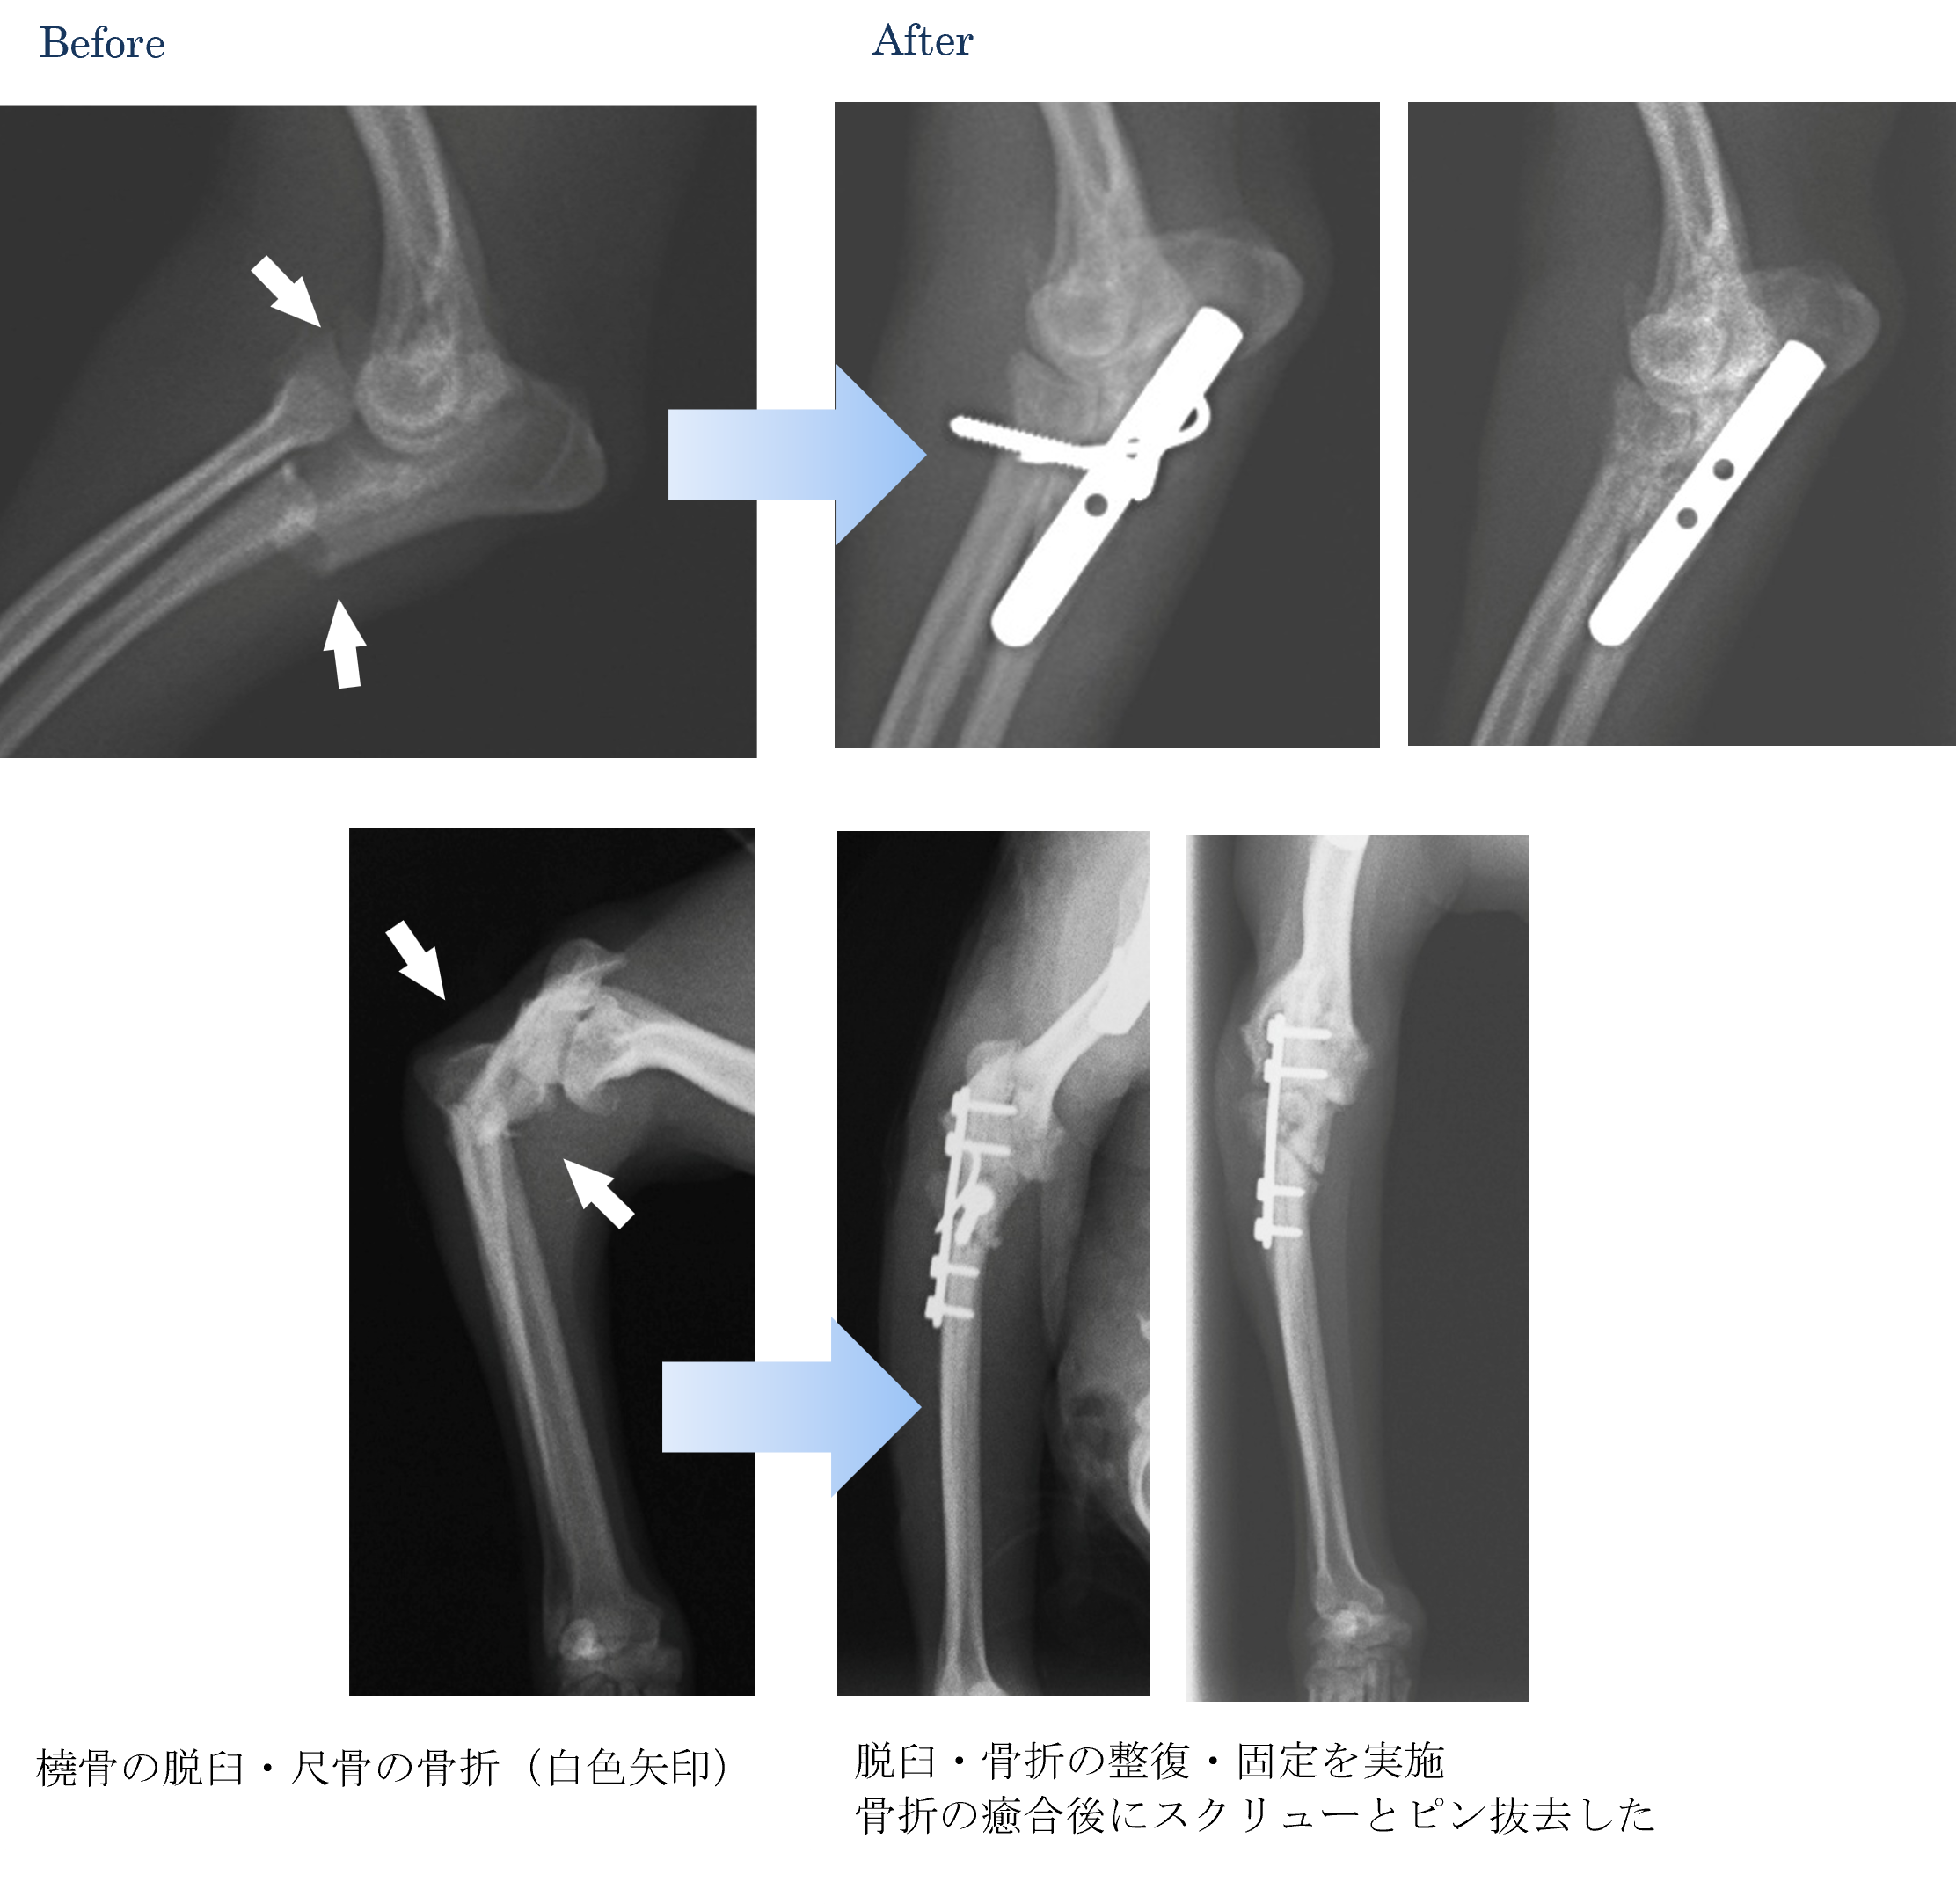

各種検査より、モンテジア骨折と診断しました。

橈骨頭の脱臼を伴う尺骨骨折をモンテジア骨折と呼びます。輪状靭帯や側副靭帯断裂、軟部組織の損傷などにより橈尺関節脱臼を伴う場合には、尺骨骨折の治療に加えて橈尺関節を安定化させる必要があります。